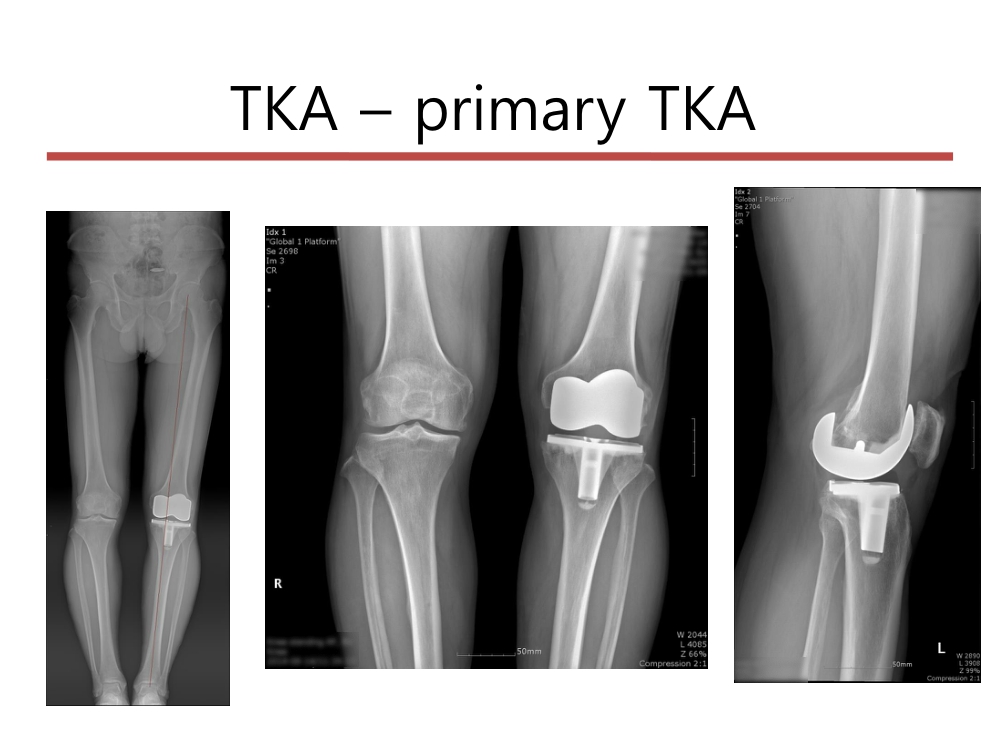

부천대성병원 윤정로 병원장님 슬관절 연수 강좌입니다.